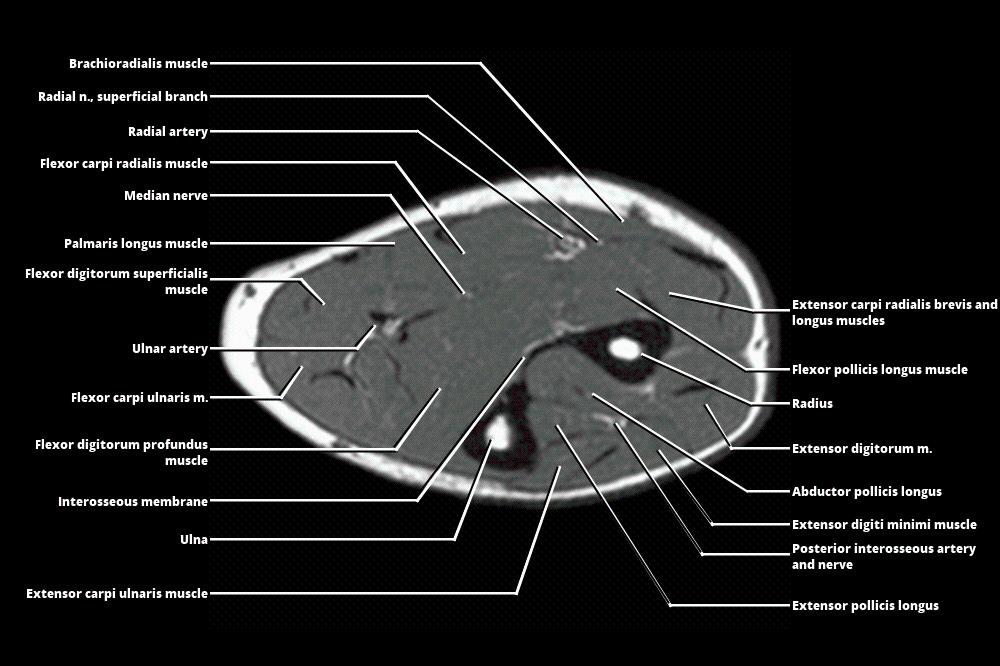

Mri Anatomy Forearm . We review the compartmental anatomy of the forearm and describe the courses of the radial, median, and ulnar nerves as they traverse the compartments. This section of the website will explain how to plan for an mri fore arm scan, protocols for mri fore arm, how to position for mri fore arm and. Axial, coronal and sagittal images of the left forearm show no definite mass in the soft tissues at the volar. Magnetic resonance imaging is particularly well suited for the medical evaluation of the musculoskeletal (msk) system including the knee, shoulder, ankle, wrist and elbow. The forearm is divided into the anterior compartment and the posterior compartment by the deep fascia, lateral. 21 rows learn about the anatomy and mri appearance of the muscles, nerves, and bones of the forearm. Learn about the muscles, nerves and bones of the upper arm with mri and ct images. Compression or entrapment of these nerves may be caused by adjacent masses but may also occur at specific transition zones along the nerve path. See tables, figures, and descriptions of the forearm. Normal mri of the forearm. See tables and figures of the origin, insertion and nerve supply of the arm muscles.

Normal mri of the forearm. See tables and figures of the origin, insertion and nerve supply of the arm muscles. Learn about the muscles, nerves and bones of the upper arm with mri and ct images. 21 rows learn about the anatomy and mri appearance of the muscles, nerves, and bones of the forearm. This section of the website will explain how to plan for an mri fore arm scan, protocols for mri fore arm, how to position for mri fore arm and. Compression or entrapment of these nerves may be caused by adjacent masses but may also occur at specific transition zones along the nerve path. We review the compartmental anatomy of the forearm and describe the courses of the radial, median, and ulnar nerves as they traverse the compartments. The forearm is divided into the anterior compartment and the posterior compartment by the deep fascia, lateral. Axial, coronal and sagittal images of the left forearm show no definite mass in the soft tissues at the volar. Magnetic resonance imaging is particularly well suited for the medical evaluation of the musculoskeletal (msk) system including the knee, shoulder, ankle, wrist and elbow.